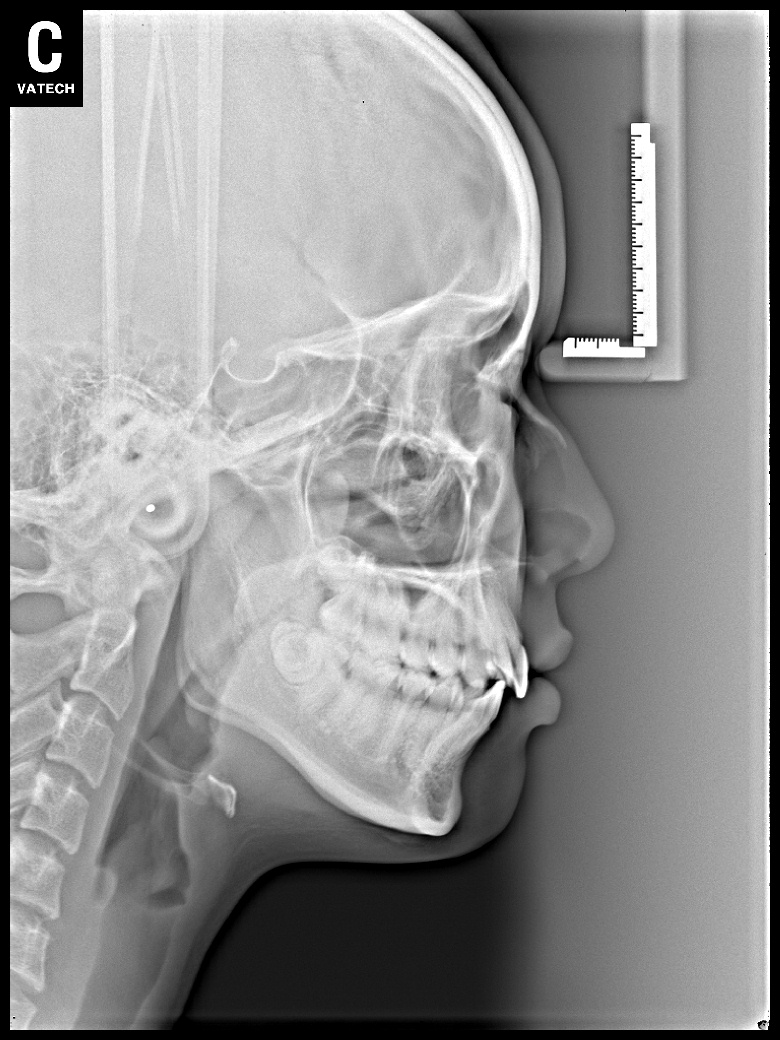

치료 전 사진입니다.